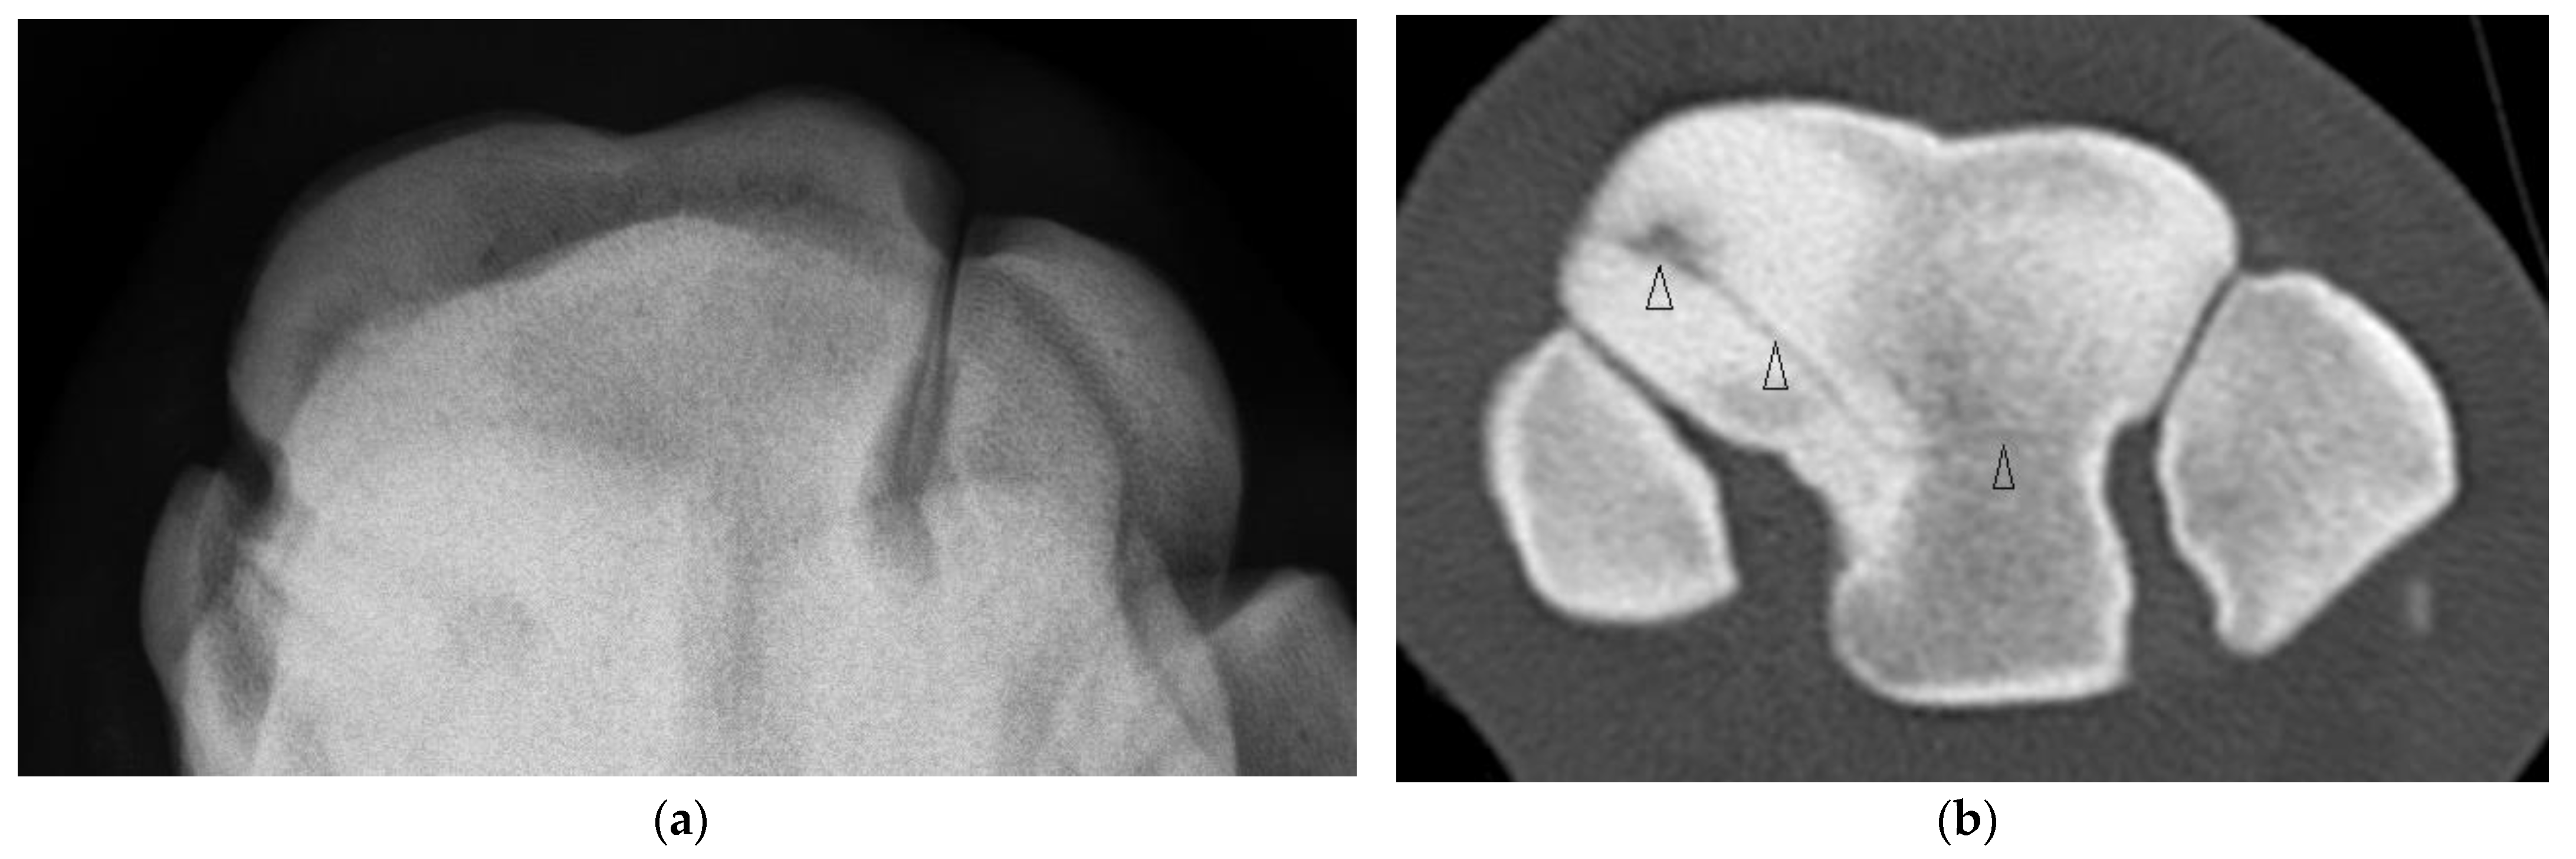

Four horses had complete fractures of variable configuration with both sagittal and frontal components. Three were corner Fx of the RaF and two of these had substantial additional fissures or fractures detected only on CT (Figure 4). The other horse had a complete Fx of both facets, with orientation that was sagittal in the RaF and frontal palmar to the InF (Figure 5); a configuration not recognized on DR.

Figure 4. Images of the left carpus of a 6-year-old thoroughbred gelding. (a) Transverse CT image through the proximal portion of the distal row of carpal bones. A comminuted corner fracture of the radial facet of the third carpal bone (C3) is evident. (b) A transverse CT image further distad reveals a large frontal fissure (arrow head). (c) Flexed dorsoproximal-dorsodistal oblique radiographic view of the distal row of carpal bones. The comminuted corner fracture was evident radiographically but the frontal fissure was not.

Figure 5. Images of the right carpus of a 3-year-old standardbred filly. (a) Flexed dorsoproximal-dorsodistal oblique radiographic view of the distal row of carpal bones. There is a vague sagittal lucency surrounded by sclerosis within the radial facet (RaF) of the third carpal bone (C3). A fracture was suspected but the configuration was unclear. (b) Transverse CT image through proximal C3. CT imaging confirmed a complete slab fracture of C3 that is sagittal within the RaF then courses in a frontal plane palmar to the intermediate facet (arrow heads). The fracture passes through a moderate sized subchondral lucency within the RaF.